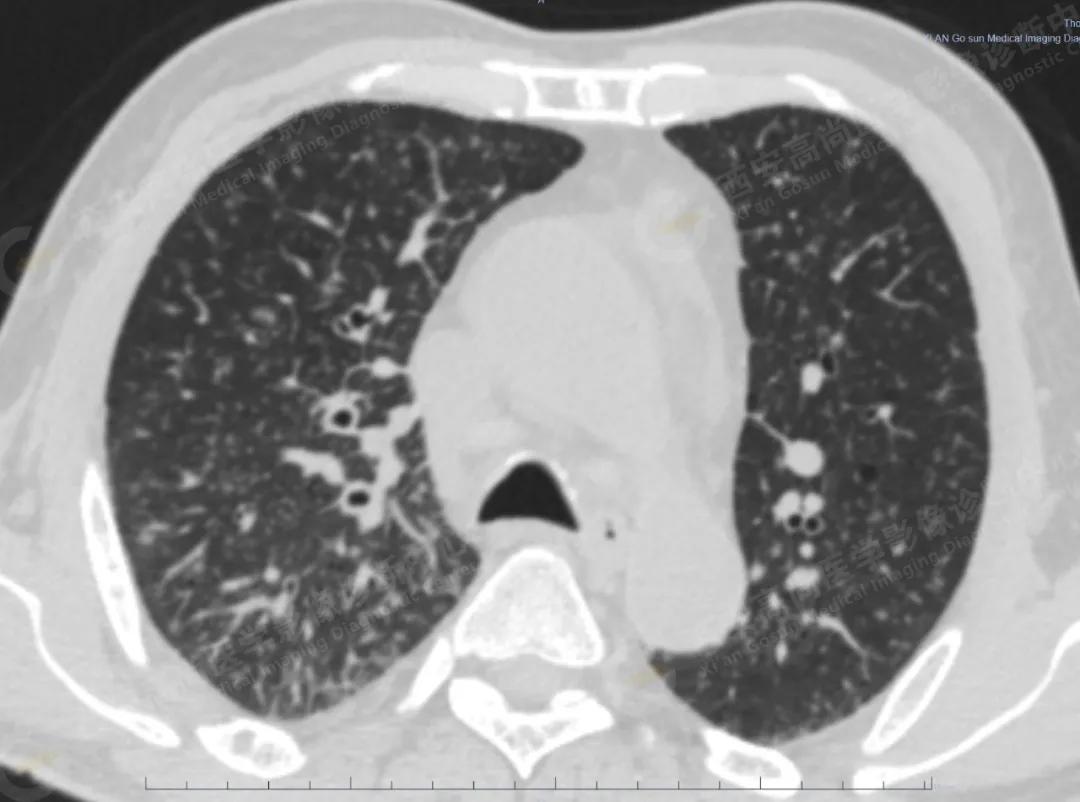

肺内弥漫性分布,肺转移瘤布满全肺

2.双肺内弥漫性分布大小不等实性小结节灶及粟粒状高密度影,均未见FDG代谢明显异常增高,均多考虑为癌性淋巴结炎及转移性病变。